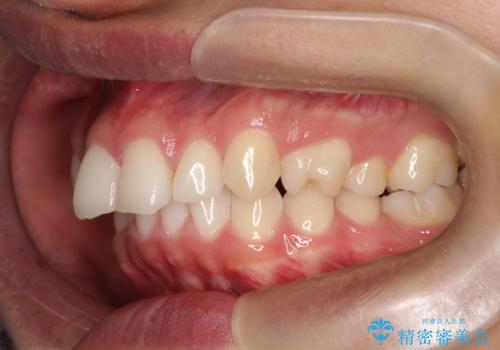

治療途中では咬み合わせの改善を目的としてバイトアップを行い、歯の捻転や叢生を改善しつつ、機能的に安定した咬合を獲得しています。

治療期間は3年2ヵ月と比較的長期となりましたが、見た目の歯並びだけでなく、咬み合わせまでしっかり整えた症例です。

上顎左右4番は90度捻転していたため、改善後歯根露出してしまっているためCTG(歯肉移植)を行う予定です。